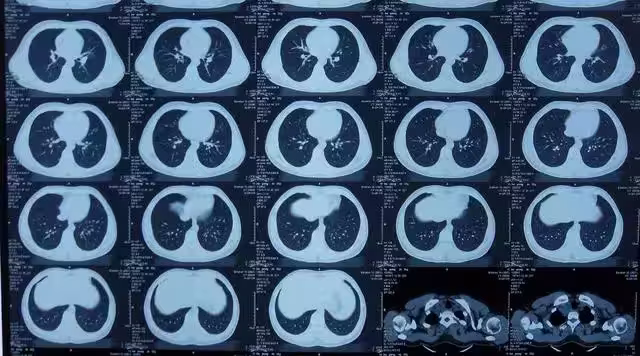

照一次CT,對身體的傷害有多大?終於有醫生肯站出來說實話

由於CT檢查的輻射劑量在安全範圍內,許多人可能會認為CT檢查是相對安全的,可以放心進行,然而,這並不意味著CT檢查沒有任何風險。

事實上,CT檢查仍然存在患癌症的風險,根據相關研究,一次效劑量為10mSv的成人腹部CT檢查將使癌症風險增加1/2000。

此外,國際輻射防護委員會(I-CRP)的研究數據表明,CT全身掃描體檢將使受檢者的輻射致癌風險增加約8%。

這意味著,如果一個人經常接受CT檢查,他們患癌症和遺傳病的風險會隨著接觸次數的增加而增大。